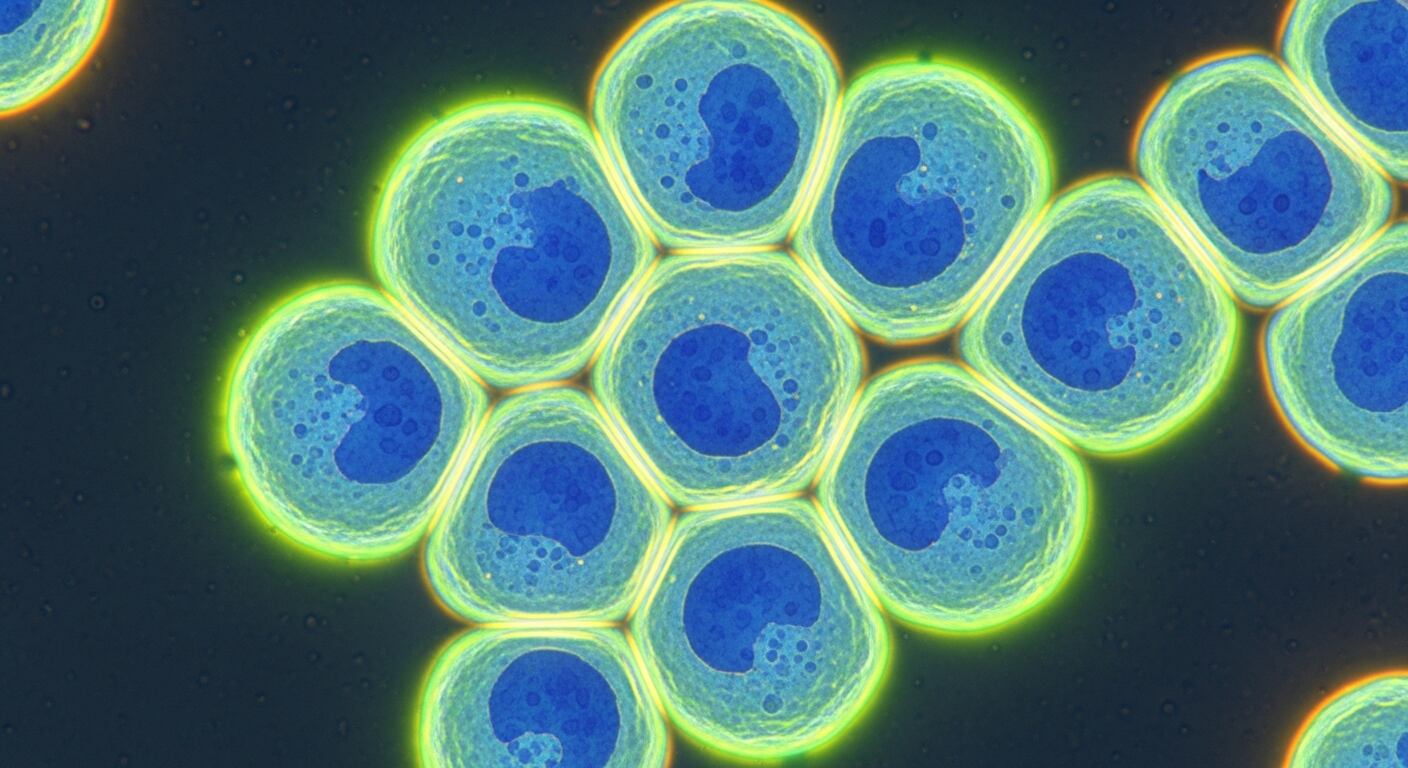

La investigación demostró que la semaglutida, un agonista del receptor del péptido similar al glucagón-1, ejerció efectos condroprotectores robustos en un modelo murino de osteoartritis asociada a obesidad. Los animales tratados mostraron menor degeneración del cartílago, reducción en la formación de osteofitos, menor daño sinovial y menor sensibilidad al dolor. Estos resultados no solo surgieron de análisis histológicos y de imágenes, sino también de evaluaciones funcionales del dolor y la movilidad.

A nivel celular, el estudio reveló que la semaglutida reprogramó el metabolismo energético de los condrocitos en condiciones inflamatorias. En lugar de depender de la glucólisis, una vía metabólica menos eficiente, las células activaron la fosforilación oxidativa. Esta restauración del equilibrio energético permitió sostener los procesos de reparación del cartílago incluso en un entorno metabólicamente adverso.

El nuevo trabajo aporta una explicación molecular concreta y desplaza el foco desde el peso corporal hacia el metabolismo celular. En la osteoartritis metabólica, el cartílago se expone a un entorno hostil, caracterizado por inflamación, estrés oxidativo, acumulación de lípidos y productos de glicación avanzada. En ese contexto, la capacidad de los condrocitos para producir energía de manera eficiente resulta clave para su supervivencia y función.